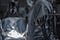

16. Abdominal Examination

‘ The abdomen is grossly distended with no localized swelling present. All quadrants move equally with respiration. There are no dilated abdominal veins. Post-cholecystectomy scar and peri-umbilical scar is visible from the previous surgery.

There is tenderness on deep palpation in the left iliac fossa and hypogastric region of the abdomen. There is no rigidity or rebound tenderness.

Bowel sounds are sluggish on auscultation.'